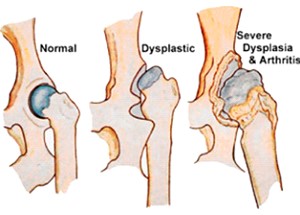

La displasia dell’anca nel Rhodesian Ridgeback

Uno studio sviluppato per OFA dal 1974 al 2010 sull’incidenza della displasia dell’anca in 147 casi ha rivelato che l’incidenza della problematica nel Rhodesian Ridgeback si attesta al 5%, una percentuale relativamente bassa in confronto ad altre razze.

Quando si parla di displasia dell’anca in un cane, ci si riferisce a una malformazione dell’articolazione coxo-femorale, la quale solitamente si presenta e si manifesta durante la crescita del cucciolo. Il cucciolo affetto da questa patologia presenterà una mancata congruenza tra testa del femore e cavità acetabolare comportando un’instabilità nei confronti dei movimenti del cane, con margini articolari che si deteriorano in maniera scorretta; la cartilagine articolare degenera, dando vita all’artrosi cronica accompagnata da dolori.

I sintomi della displasia dell’anca legati a un cane adulto riguardano l’artrosi, ormai sviluppatasi nel corso degli anni. Anche in questo caso, l’intensità del dolore varia secondo la gravità della patologia. Per eseguire una diagnosi corretta bisognerà sottoporre il cane a radiografie mirate, si consiglia una diagnosi precoce intorno ai 4 -6 mesi di vita, una procedura particolarmente utile, poiché esistono interventi di tipo correttivo che possono essere applicati solo in fase di crescita non compiuta. Tale diagnosi è emessa da un veterinario ortopedico a seguito di visita clinica, osservazione dell’andatura e della postura, manipolazione e radiografie con sedazione. A seguito del risultato emerso dalla radiografia, è possibile definire il grado di displasia dell’anca, ovvero:

Grado A, non c’è displasia dell’anca partendo dalla testa del femore fino ad acetabolo e congruenti;

Grado B, l’articolazione dell’anca si presenta quasi normale, mentre la testa del femore e l’acetabolo sono di poco incongruenti;

Grado C, ove sarà diagnostica una leggera displasia dell’anca, con testa del femore e acetabolo incongruenti e piccoli segni artrosici;

Grado D, ovvero media displasia dell’anca, con testa del femore e acetabolo evidentemente incongruenti e presenza di artrosi;

Grado E, grave displasia dell’anca, con importanti modificazioni dell’anca e possibile lussazione o sub lussazione della medesima. Inoltre, si avrà un’importante deformazione della testa del femore, che si presenterà a fungo o appiattita, oltre alla presenza di una forte artrosi.